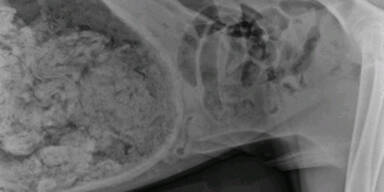

Der Besitzer einer drei Jahre alten Dänischen Dogge brachte sein Tier ins Krankenhaus, weil es sich schlecht zu fühlen schien. Im Krankenhaus in Portland  (USA) dann die Überraschung: Die Dogge hatte eigenartiges Material im Magen.

Nach einer rund zweistündigen OP herrschte Klarheit, der Hund hatte 43 und eine halbe Socke gefressen. Krankenhaus-Sprecherin Shawna Harch meint, dass es der wohl ungewöhnlichste Fall in der Geschichte des Krankenhauses ist.

So ungewöhnlich, dass die Fotos einen Wettbewerb mit dem Titel "Sie haben WAS gefressen?" gewannen.